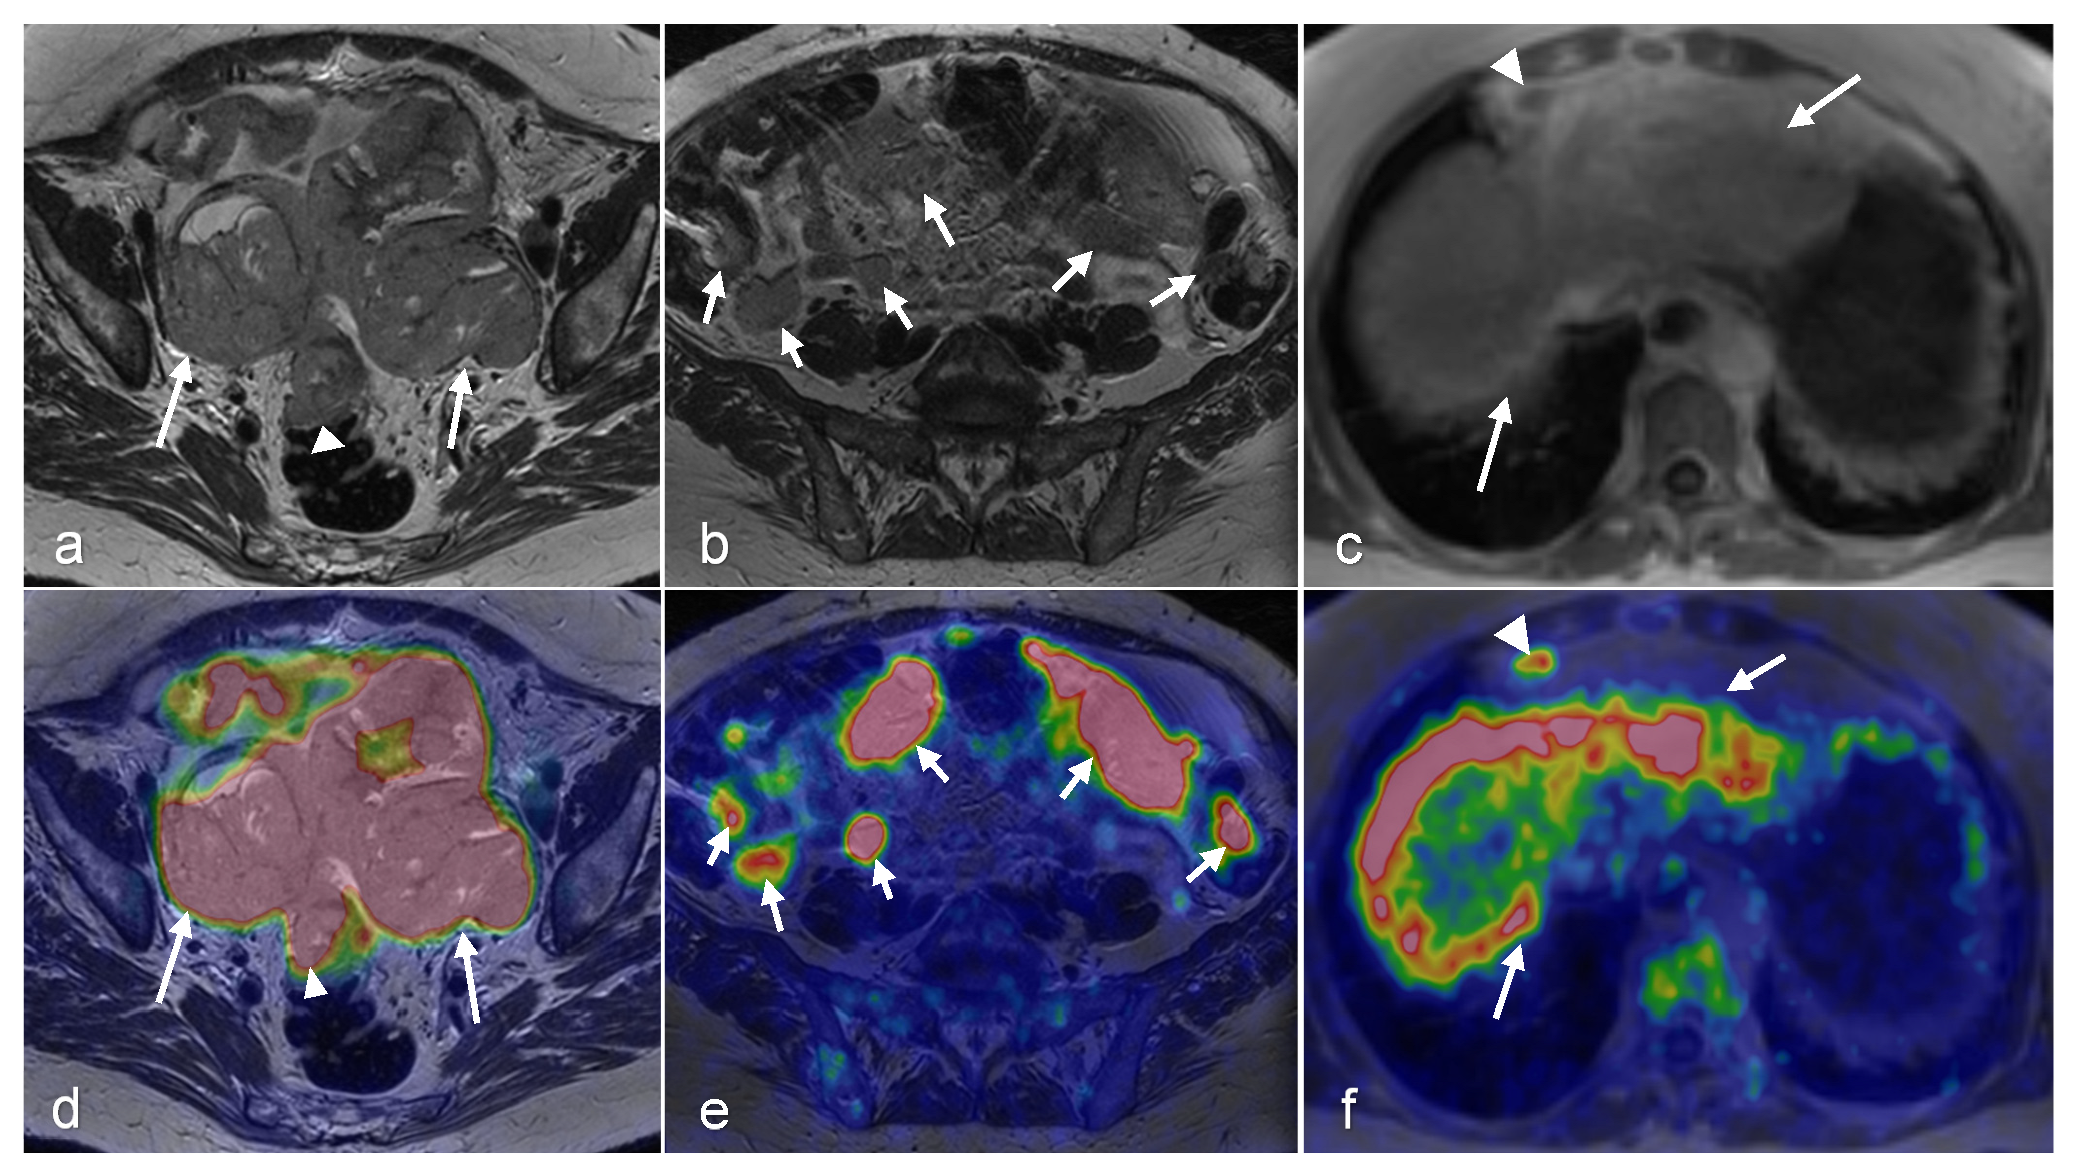

3.3. Ovarian Cancer

- Xi, Y.; Sun, L.; Che, X.; Huang, X.; Liu, H.; Wang, Q.; Meng, H.; Miao, Y.; Qu, Q.; Hai, W.; et al. A comparative study of [(68)Ga]Ga-FAPI-04 PET/MR and [18F]FDG PET/CT in the diagnostic accuracy and resectability prediction of ovarian cancer. Eur. J. Nucl. Med. Mol. Imaging 2023, 50, 2885–2898. [Google Scholar] [CrossRef]

- Nie, J.; Zhang, J.; Gao, J.; Guo, L.; Zhou, H.; Hu, Y.; Zhu, C.; Li, Q.; Ma, X. Diagnostic role of 18F-FDG PET/MRI in patients with gynecological malignancies of the pelvis: A systematic review and meta-analysis. PLoS ONE 2017, 12, e0175401. [Google Scholar] [CrossRef]

| Ovarian | Benefit(s) | Evaluates for metastatic disease and possible lymph node involvement. Useful for determining response to chemotherapy, can predict diaphragm and omental involvement [32] | Outperforms CT and PET/CT for detecting ovarian cancer [33] Helps differentiate between benign, malignant, and borderline masses by DCE-MRI and DWI [34] Useful for treatment planning in advanced ovarian cancer [32] | Evaluating possible metastatic extraperitoneal spread of the disease and metastatic lymph nodes [32] Detects recurrent disease [32] predicts treatment response after NAC [35,36,37,38,39,40] | Hybrid molecular and anatomic imaging provides high soft tissue contrast with lower radiation dose Detects lymph node metastases with high accuracy [32] |

| Pitfall(s) | Limited soft tissue evaluation and differentiation. Limited in evaluating local extent of disease | Limited sensitivity in detecting small peritoneal implants [41] | Lack of reliable differentiation between borderline and benign tumors according to ESGO/ISUOG/IOTA/ESGE Consensus Statement on pre-operative diagnosis of ovarian tumors. No clear cut-off value for maximum standardized uptake value for differentiation between benign and malignant ovarian tumors [32] Not recommended for primary detection of ovarian cancer [32] The physiologic FDG uptake in pre-menopausal ovaries can be mistaken with malignancy [25,26,27] | Less sensitive for detection of pulmonary nodules compared with PET/CT | |